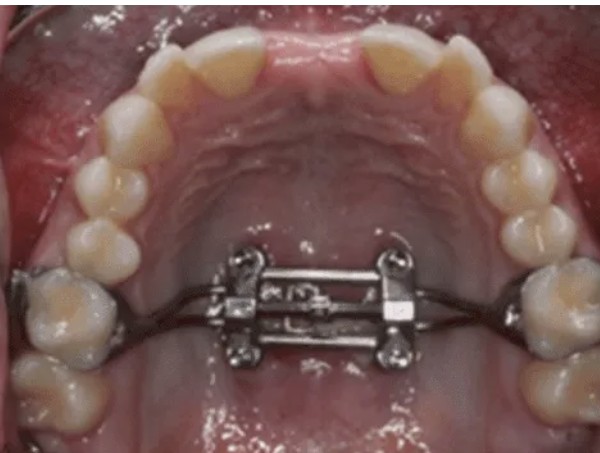

- Small cuts are made in the upper jawbone and a jaw expansion appliance is fitted to the roof of your mouth.

- Jaw widening begins about three days after surgery, when gradual adjustments to the appliance start.

- This palate expansion surgery phase continues over several weeks.

- Once the upper jaw has reached the target width, the appliance stays in place for a few months to allow the bone to consolidate.

While the jaw expansion appliance is in place, brush carefully with a soft toothbrush and rinse with warm salt water after meals. Dr. Kristian van Mourik and your orthodontist will review your progress at regular intervals to confirm that upper jaw expansion is proceeding as planned.